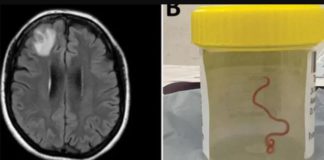

Live worm found in woman’s brain during surgery